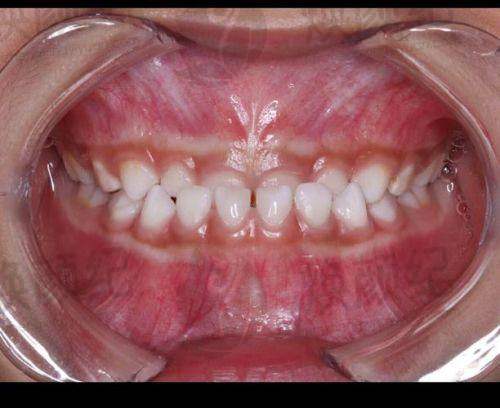

5. 金属非自锁托槽矫正:通过金属托槽和弓丝的力量,使牙齿移动到正常位置。主要解决牙齿不齐、拥挤等问题。叶莹医生的临床经验表明,矫正过程中患者要按时复诊,注意口腔卫生,避免食用实力强食物。适用于大多数牙齿畸形患者。

6. 地包天:地包天是一种常见的牙齿错颌畸形,可通过正畸或正颌手术治疗。叶莹医生强调早期干预的重要性,对于儿童患者可采用功能矫治器,成人可能需要正畸正颌联合治疗。适用于有地包天问题的患者。